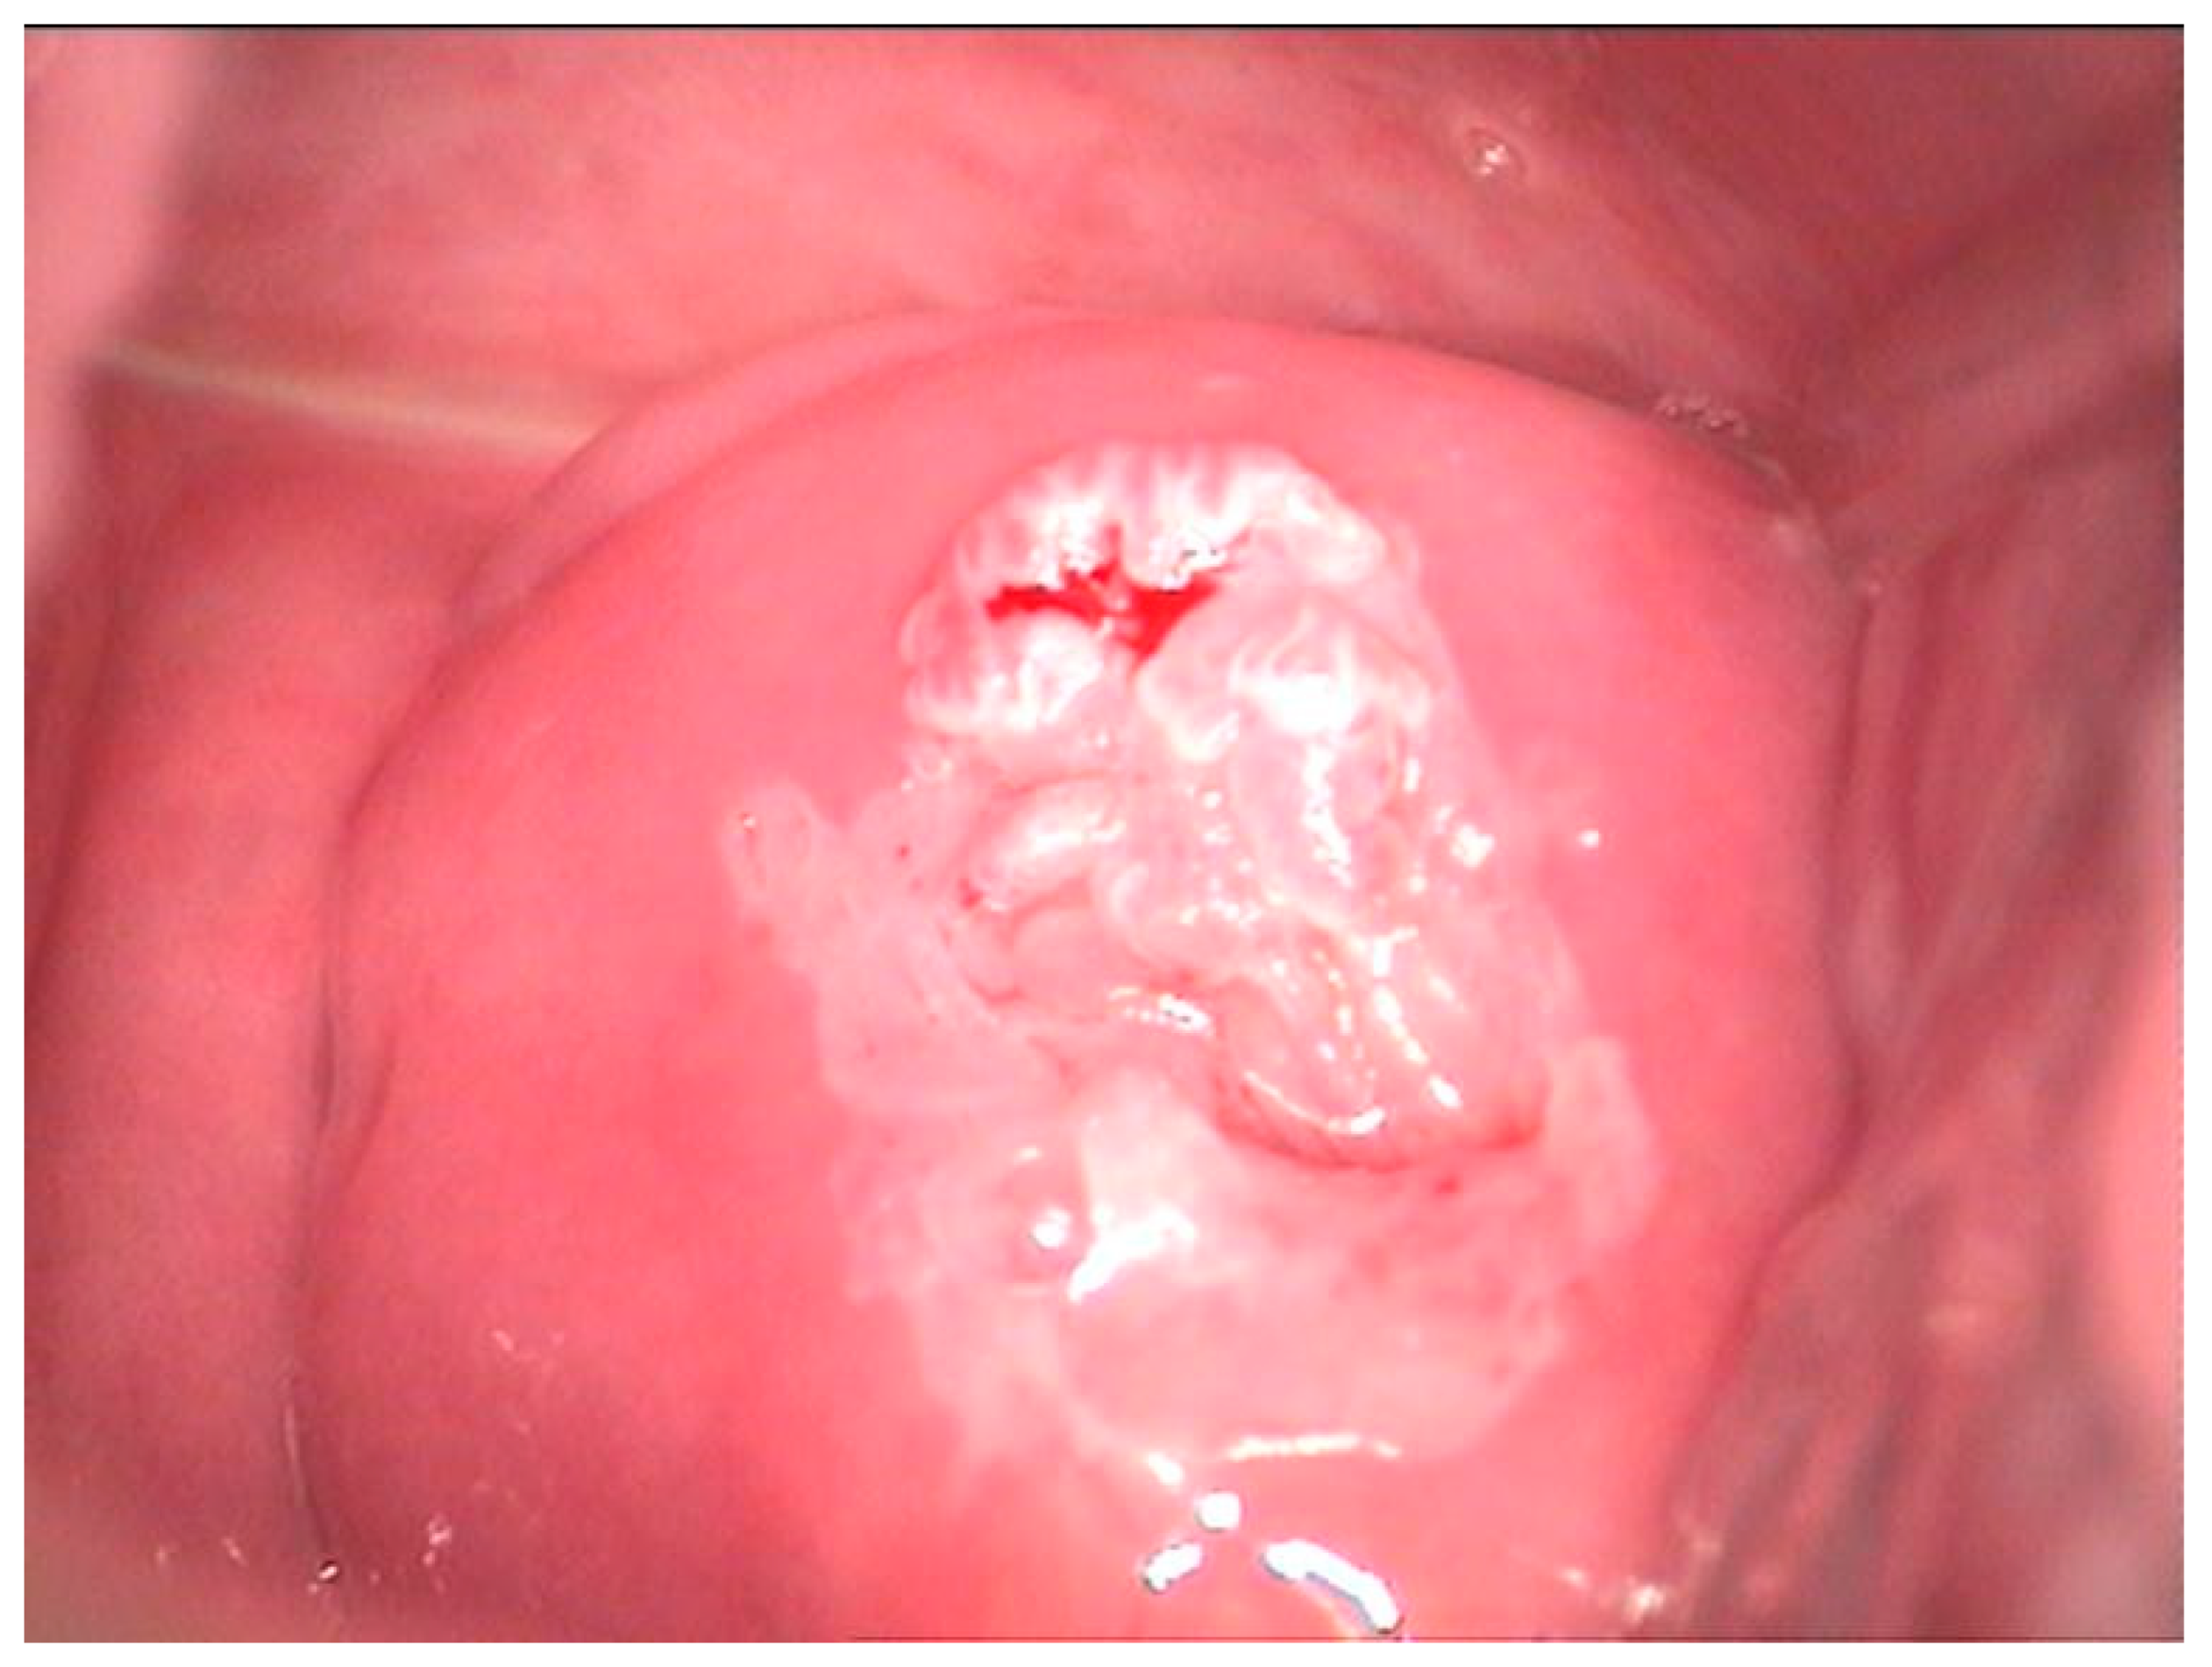

2.2. Clinical Examination